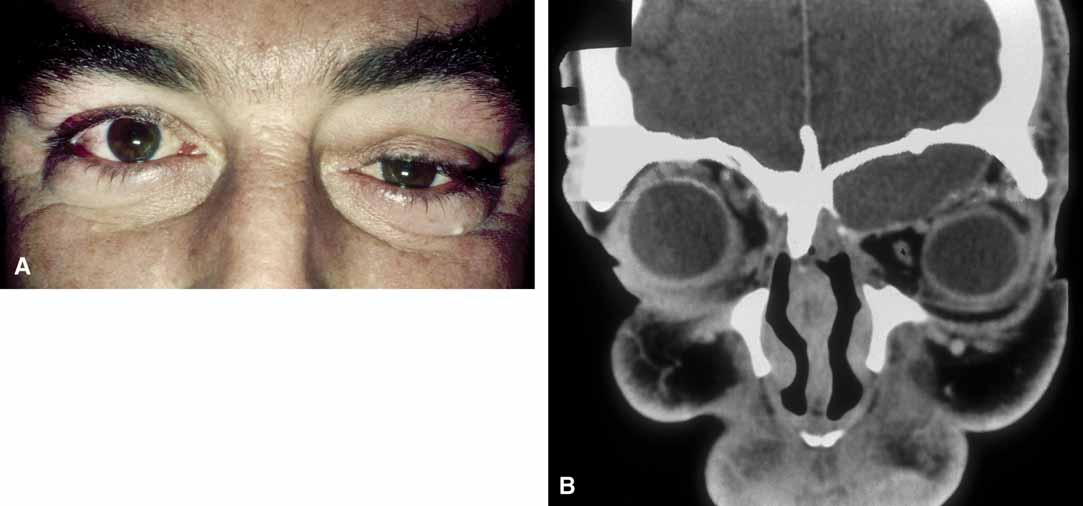

Mucoceles of the frontal and ethmoid sinuses are most common; and their clinical features are usually related to a mass effect and inflammation.33–34 The enlargement of the mucocele may be insidious, with proptosis and displacement of the globe being manifest in association with a palpable, smooth-walled mass in the upper inner quadrant of the orbit (Fig. 8).

Fig. 8 Frontal sinus mucocele in a man with a history of sinus disease. A. The left eye is displaced inferotemporally, indicating the superior medial location. B. Coronal section of a computed tomogram shows expansion of the opacified left frontal sinus with loss of the bony anterior and inferior walls of the frontal sinus.